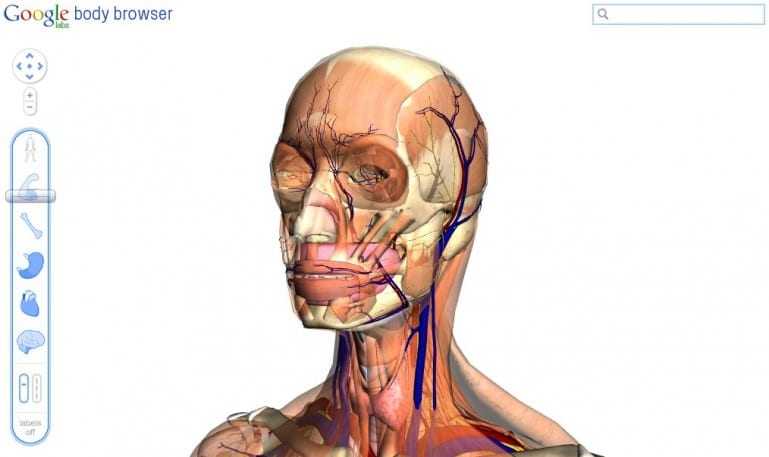

Αν και ακόμη σε πειραματικό στάδιο το Body Browser επιτρέπει σε χρήστες να ‘τεμαχίζουν’ το ανθρώπινο σώμα μέσα από τις στρώσεις του σώματος σε ένα τρισδιάστατο μοντέλο. Με χρήση εικονικών ‘μαχαιριών’ γίνεται εύκολα η εξερεύνηση των οργάνων που μας κάνουν να… λειτουργούμε.

Στήθηκε για να είναι και μια επίδειξη της τεχνολογίας WebGL, επιτρέπει σε έναν browser να σχηματίζει 3D γραφικά χωρίς να υπάρχει ανάγκη για plugins. Το Body Browser για την ώρα είναι δουλειά που στήνεται στα Google Labs και όποιος έχει έναν WebGL-enabled browser – όπως οι τελευταίες εκδόσεις των Chrome και Firefox για Windows και ο Safari για Mac – θα πρέπει να μπορούνε να ‘εισέλθουν’ σε πολλαπλές στρώσεις, να κάνουν zoom in και out, και να αναζητούν συγκεκριμένα μέρη του σώματος όπως κάνουμε για τις πόλεις του Google Maps.

Είναι μια εντυπωσιακή επίδειξη της HTML5 και WebGL τεχνολογίας και πραγματικά θα δούμε πολλά ωραία με αυτή αφού έτσι δεν χρειάζεται να χρησιμοποιούνται δυνατές κάρτες γραφικών.